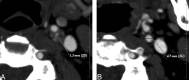

Fig 6.

Underestimation of stenosis in DSA. A, An axial MIP image from the left ICA stenosis graded severe by CTA (arrow). According to the vessel analysis method (B, C) the stenosis is 77%. In DSA, the maximum stenosis is 50% (D). In surgery, the stenosis turned out to be severe.